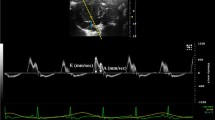

At the age of 20 weeks, all echocardiographic parameters compared among the three comparison groups (Table 3). Echocardiography performed at the age of 40 weeks, after the completion of treatments, revealed that while LVEDS, LVEDD and LV FS (%), as indices of LV systolic function, showed no significant differences among the three comparison groups, Doppler indices of mitral valve flow, reflecting LV diastolic function, showed that the E and A velocities of the UT-OLETF groups were significantly lower than those of the LETO and RT-OLETF groups (p < 0.05). The E/A ratio was 1.7 ± 0.1, 1.5 ± 0.1 and 1.7 ± 0.1 in the LETO, UT-OLEFT and RT-OLETF groups, respectively. The E/A ratio of the RT-OLETF group was significantly higher than that of the UT-OLETF (p < 0.05). In addition, deceleration time (DT) and LV isovolumic relaxation time (IVRT) were significantly decreased in the RT-OLETF group compared to the UT-OLETF group (Table 4; Fig. 1). Therefore, while improvement in LV diastolic dysfunction was clearly observed in rosiglitazone -treated T2D rats compared to untreated T2D rats, there was no improvement in LV systolic function.

Comparison of left ventricular mitral inflow patterns at the age of 40 weeks. The early to late diastolic peak velocity (E/A) ratio was reduced and the deceleration time (DT) of early diastolic inflow was increased in the OLETF rats (middle). These parameters were normalized in the rosiglitazone-treated OLETF rats (right). E early diastolic peak velocity, A late diastolic peak velocity